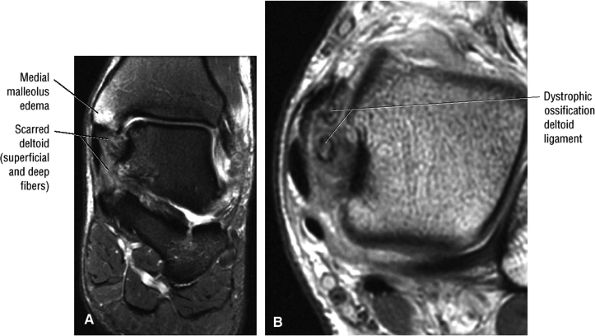

fascicle inserts onto the superior border of the calcaneona vicular ligament. The deep part of the deltoid, which is rectangular, consists of a small anterior component (the anterior tibiotalar ligament) and a strong posterior component (the posterior tibiotalar ligament) (Fig. 5.64). The posterior tibiotalar ligament represents the strongest part of the entire medial ligament complex. The deep portion of the deltoid ligament, covered by synovium, is intra-articular.

![]() |

|

FIGURE 5.58 ● transverse section through the midcalf shows the anterior and lateral compartments and their contents.